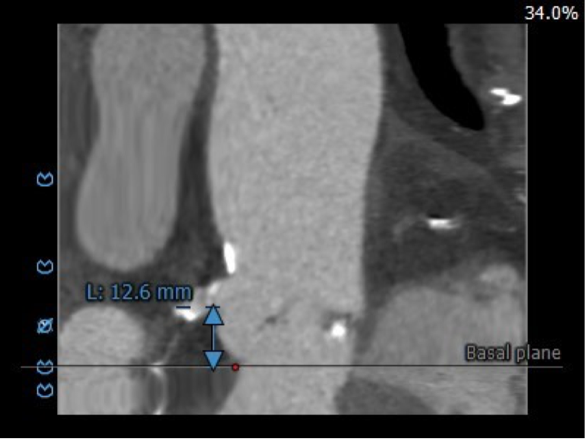

主动脉根部评估

CT 数据显示该患者为三叶式主动脉瓣